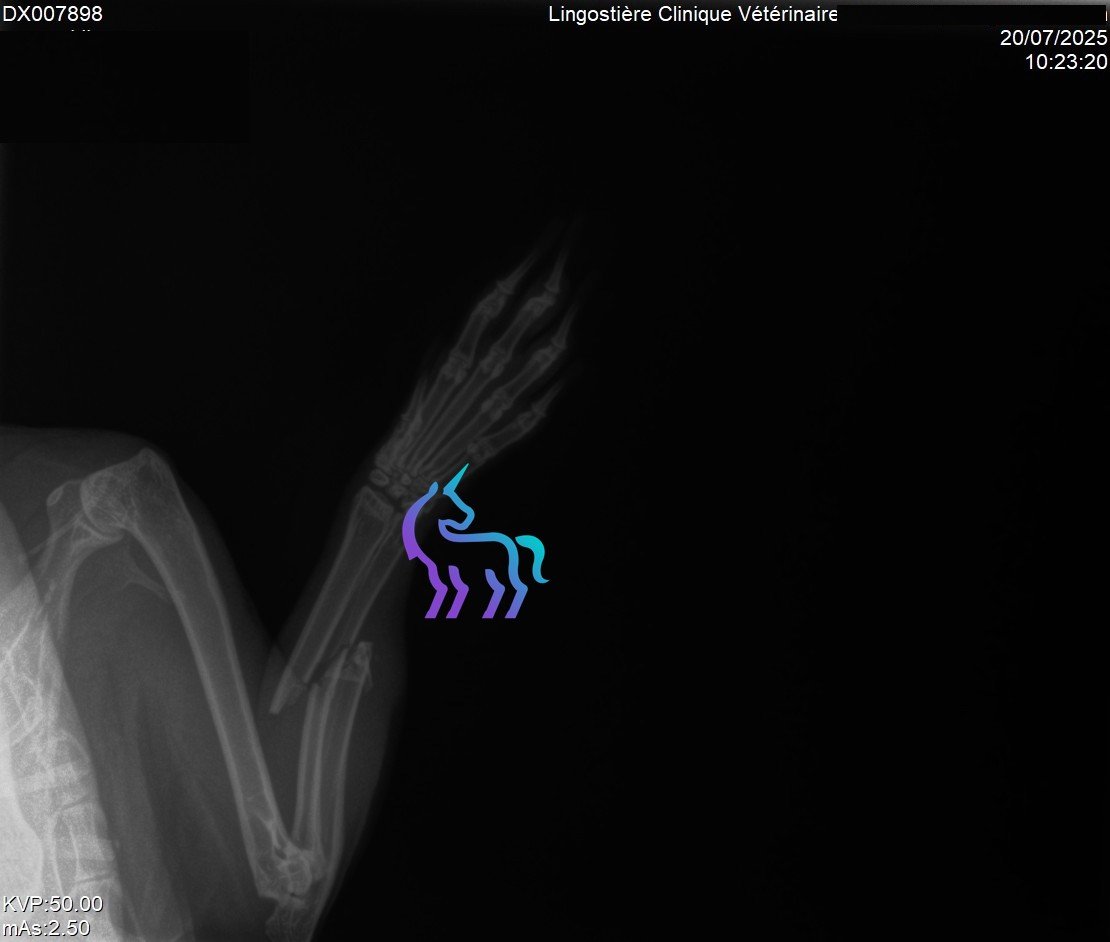

Oui (bassin, membres). Une douleur importante peut entraîner anorexie puis stase digestive.

Quels examens sont utiles ?

Radiographies pour fractures/arthrose, scanner/IRM si suspicion lésion vertébrale.Amputation : dans quels cas ?